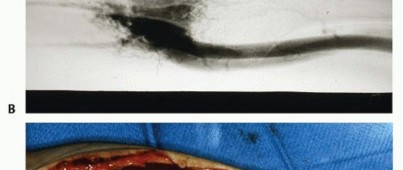

True aneurysms account for 6% of all tumors of the hand.24True aneurysms, most notably hypothenar hammer syndrome, usually follow blunt trauma in the area of the vessel. The trauma may be a single event or repeated injury. The vessel dilates in response to injury to the arterial media, leading to fusiform vessel enlargement.Aneurysms also occur secondary to disease processes such as arteriosclerosis, metabolic disorders, Kawasaki disease, Buerger disease, hemophilia, osteogenesis imperfecta tarda, granulomatous arteritis, and cystic adventitial disease (FIG 8).20

PSEUDOANEURYSMS

Pseudoaneurysms account for most (83%) aneurysms of the hand and generally occur on the palmar surface of the hand.They may be secondary to a puncture wound (such as from a knife or pencil) or complete rupture of the vesselwall with continuity maintained by the surrounding soft tissues.20,24 They typically present with significant soft tissue swelling (FIG 9).Pseudoaneurysms develop slowly over time and are usually not evident for weeks to months after the injury. A bruit may be noted on examination. Like true aneurysms, the most common vessel is in the ulnar artery.